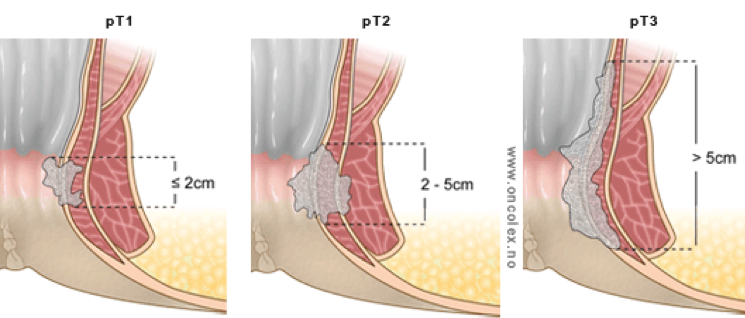

Den kliniska och radiologiska utredningen ska utmynna i att tumören stadieindelas enligt TNM (tabell 1 och figur 5). Den senaste TNM-versionen för analcancer (TNM8) lanserades 2015. Efter en övergångsperiod då både version 7 och 8 användes parallellt, gick vi i Sverige helt över till TNM 8 den 1 januari 2020. Notera dock att de uppgifter som matas in i kvalitetsregistret leder till att stadium anges både enligt TNM7 och TNM8, för att möjliggöra jämförelser med tidigare årskohorter.

Tabell 1. Stadieindelning av analcancer enligt TNM (UICC), version 8 (2015).

T1 |

Tumör ≤ 2 cm |

T2 |

Tumör > 2 cm men ≤ 5 cm |

T3 |

Tumör > 5 cm |

Figur 5. Schematisk bild av T-stadium vid analcancer